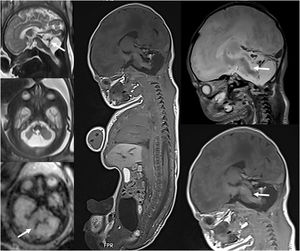

Avances en imagen post mortem (PM)Su práctica pediátrica se está generalizando tras la disminución gradual de las autopsias invasivas y la mayor aceptación por parte de padres y profesionales sanitarios. Incluye diversas técnicas de imagen, como radiografías convencionales, TC o RM. Las radiografías siguen siendo la base de la imagen post mortem forense en casos de muertes infantiles sospechosas. Numerosos estudios han demostrado la utilidad de la RM PM en la imagen perinatal y fetal debido a su capacidad para visualizar anomalías de tejidos blandos, si bien la TC PM ofrece ventajas para la identificación de fracturas, menor coste y mayor rapidez de adquisición4. La guía estándar del Reino Unido en casos sospechosos de maltrato físico infantil se actualizó en 2018, e incluye ahora la recomendación de una TC PM si hay sospecha de lesión ósea que no se haya determinado mediante radiografía, así como una RM PM si hay sospecha de lesión de tejidos blandos en muertes pediátricas inesperadas. La RM PM se realiza en fetos o neonatos preferentemente, con una RM de cuerpo entero, obtenida en menos de 24horas tras el parto o el fallecimiento (figura 3). Se precisa una formación radiológica previa para reconocer los hallazgos normales post mortem y diferenciarlos de los verdaderamente patológicos. Puede no ser diagnóstica en casos de fetos con poca edad gestacional.

Feto de 33 semanas de gestación con hallazgo ecográfico de hipoplasia cerebelosa. A)RM fetal realizada a las 33 semanas, que demuestra una lesión clástica o destructiva del cerebelo con restos hemorrágicos (flechas). B)RM fetal post mortem tras la interrupción de la gestación que muestra la hemorragia cerebelosa, con hallazgo asociado de lesión tegmental del bulbo raquídeo (flechas), no evidenciada previamente.